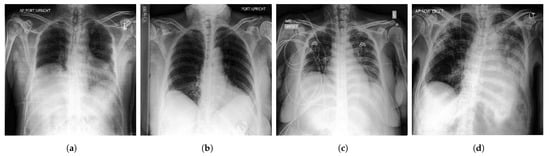

3.2. Enhancement

Image enhancement techniques are generally used to improve the information interpretability in images. For CXR images, these techniques are used to provide a better image quality to human readers (radiologists) as well as to automated systems [71]. To improve the quality of a CXR image, multiple parameters can be considered (contrast, brightness, noise suppression, edge of features, and sharpness of edges) using different methods including histogram equalization (HE) [72], high and low pass filtering [73], and unsharp masking [74]. Figure 5 depicts an example of enhancement applied to a CXR image.

Figure 5.

(a) Noisy CXR image from a low quality version of CheXpert dataset [44]; (b) Enhanced CXR image.